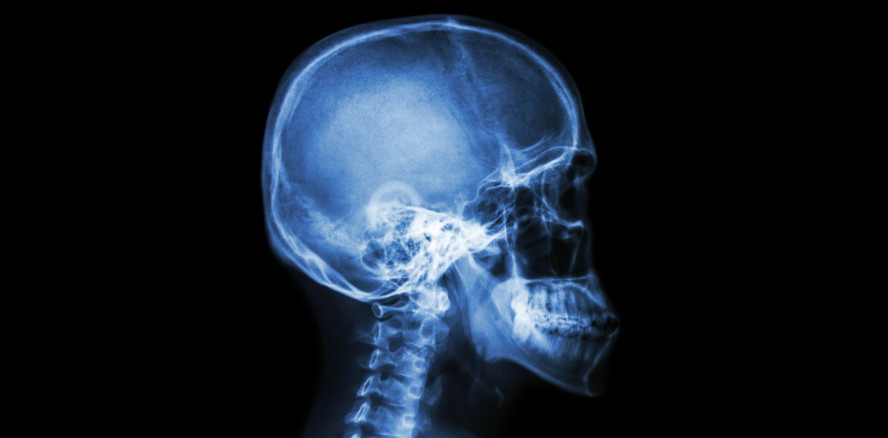

Als nach dem Spiel Röntgenaufnahmen seines Kiefers gemacht wurden, war die Überraschung groß: Vesey war eigentlich der Meinung, dass er seine Zähne verloren hatte, doch das Röntgenbild zeigte das Gegenteil. Die Zähne waren noch da, nur an einer anderen Stelle als vermutet. In der Unterlippe, die nach dem Zusammenstoß aufgeplatzt und blutig war, fanden sich die Zähne wieder.